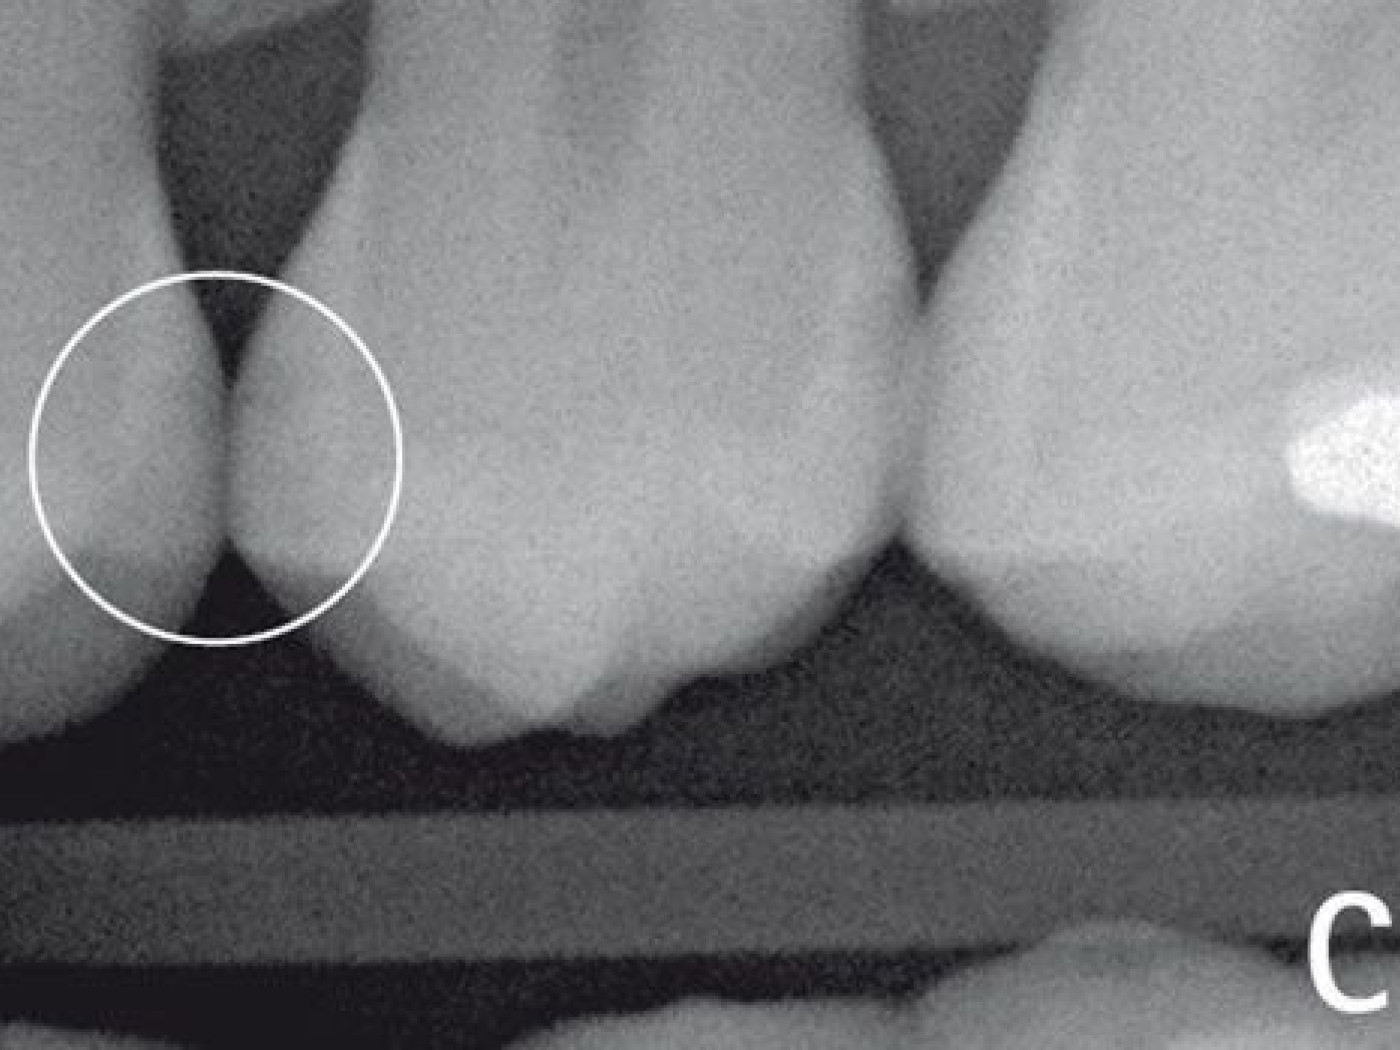

На рис. (А) представлены премоляры, которые кажутся клинически здоровыми. Затемненные участки заметны только на рисунке (B) (левый и правый круг), полученном при помощи DIAGNOcam. Кариозные изменения также заметны на рентгеновских снимках на задней поверхности. С помощью рентгеновского излучения переднюю область зуба оценить не всегда возможно в связи с эффектом частичного наложения (C), которое возникает довольно часто.